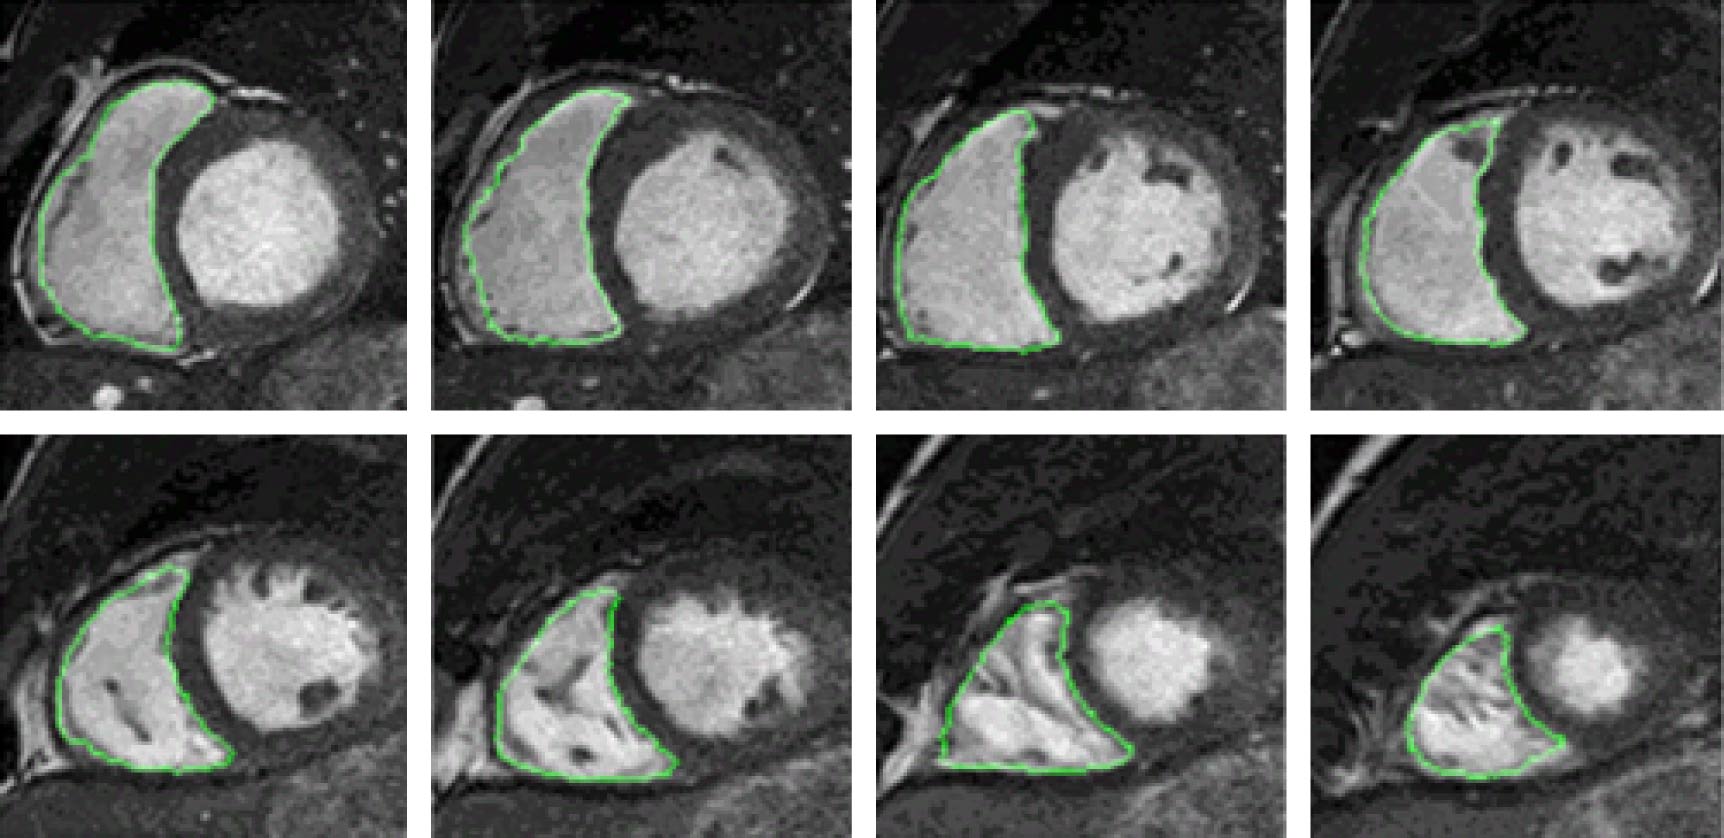

Segmentation of right ventricle (RV) in a cine cardiac magnetic resonance (CMR) image is essential for the diagnosis and therapy of cardiac diseases. Traditional image segmentation methods fail to achieve high accuracy due to the complex structure of RV. Multi-atlas frame, which transforms the segmentation into registration and fusion, has become one of the main segmentation methods of RV in recent years. In this paper, we suggest a new multi-atlas frame for the automatical and accurate segmentation of RV. Firstly, an adaptive affinity propagation algorithm is used to obtain a series of atlases, in which the atlas set most similar to the target image based on hausdorff distance and normalized mutual information is selected. Then, the target image is registered onto the selected atlas by using multi-resolution strategy-based affine transform and Diffeomorphic demons algorithm to generate a deformation field, which is applied to the label image to obtain coarse segmentation results of RV. Finally, the Consensus Level, Labeler Accuracy and Truth Estimation (COLLATE) algorithm is used to fuse the coarse segmentation result to obtain the RV. The 30 cine CMR datasets are applied to the retrospective analysis. The comparison between RV value from the present algorithm and that from the manual segmentation shows that the average dice index and hausdorff distance are 0.84 and 11.46 mm, respectively, the correlation coefficients and deviation means of endo-diastolic volume, endo-systolic volume and ejection fraction are 0.94, 0.90, 0.86, and 2.5113, –3.4783, 0.0341, respectively. Compared with convolutional neural networks, the new multi-atlas frame has an endo-systolic volume close to the manual result. The results show that the suggested method improves the accuracy and robustness of segmentation of RV from the effective atlas selection and multi-resolution Diffeomorphic demons algorithm-based registration, and it promises to be applied to clinical diagnosis.